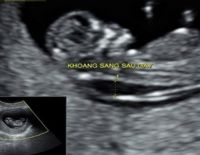

Đo độ mờ da gáy là gì và ý nghĩa khi thực hiện trong thai kỳ

Một trong những kiểm tra cần thiết trong thai kỳ mẹ cần thực hiện là đo độ mờ da gáy. Việc đánh giá thai nhi có nguy cơ bị bệnh Down hay không chính là nhờ vào phương pháp này. Tuy nhiên, tính chính xác...

Độ mờ da gáy 1.5 khi thai 12 tuần có bình thường không?

Độ mờ da gáy 1.5 có phải là chỉ số bình thường không khi thai được 12 tuần tuổi. Đây là bước siêu âm thai quan trọng trong 3 tháng đầu mà mẹ bầu cần thực hiện để chẩn đoán các dị tật bẩm sinh...